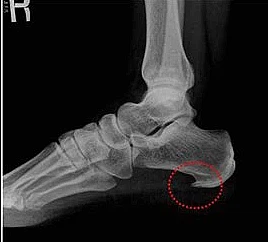

족저근막염은 쉽게 말해 발바닥 근육을 덮고 있는 막에 생긴 염증을 의미합니다. 족저근막은 발뒤꿈치뼈부터 발끝까지 이어지는 두껍고 강한 섬유로 발의 아치를 지탱해 발밑에 전달해지는 충격을 흡수하고 보행 시 발의 기둥이 되는 부분입니다.

이런 족저근막에 반복적인 미세 손상이 발생하게 되면 근막을 조직하는 콜라겐의 변성이 발생하며 이로 말미암아 염증과 진통을 보이는 질환을 족저근막염이라고 합니다.

족저근막에 이상이 발생하면 발뒤꿈치에 진통이 나타납니다. 진통이 내부 깊숙한 곳으로부터 나타나는데, 증상이 심할 때는 발 전체가 아파 서있기도 힘듭니다.